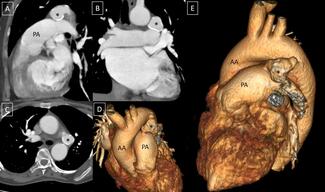

A 46-year-old woman presented with complaints of shortness of breath (New York Heart Association II) for the past 3 years. There was no history of orthopnea or paroxysmal nocturnal dyspnea, nor of trauma or previous aortic or cardiovascular...